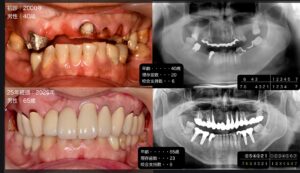

今年のテーマは前歯…様々な角度からのプレゼンは本当に楽しく勉強になります。